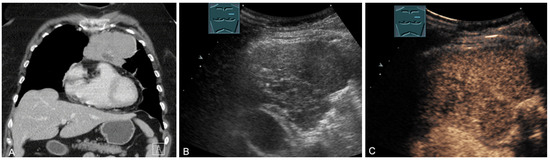

Figure 14.

A cystic mediastinal mass on CT (provided by Prof. Dr. Andreas H. Mahnken, Marburg, Germany) (A), B-mode US (B), and CEUS (C), surgically confirmed as a mediastinally located bronchogenic cyst.